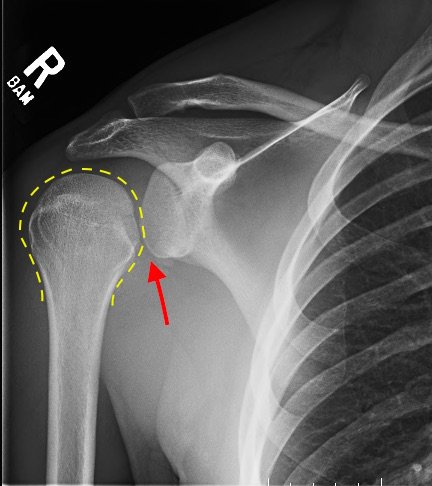

Posterior Shoulder Dislocation, AP XR, Annotated. JETem 2017